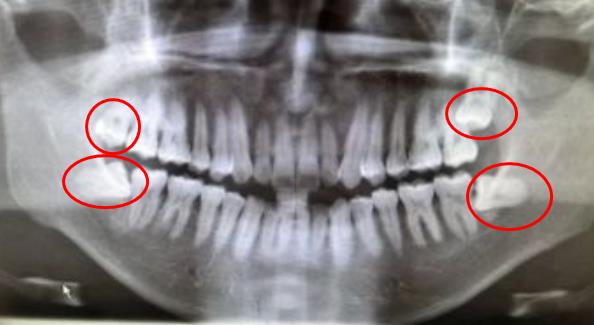

難拔的智齒圖

智齒拍片,如圖所示,這個(ge) **有4顆智齒